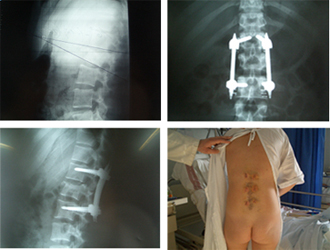

Imágenes de una artrodesis vertebral por técnica mínimanente invasiva donde puede apreciarse el abordaje de la zona intersomática para la colocación de espaciadores con injerto y de la instrumentación posterior.

Escoliosis tratada por técnica mínimamente invasiva con imágenes radiográficas y de las cicatrices a los dos años de la intervención.